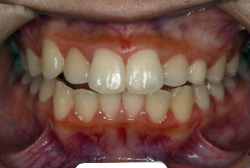

第2段階としてマルチブラケット法を非抜歯で1年間行いました。歯の傾斜が修正され、正中も一致し、美しく機能的な配列に仕上がりました。再診時に確保した隙間をすべて使って、すべての永久歯を理想的な位置に配列することができました。前傾していた上の前歯は真っ直ぐに直立し、完全な正常咬合が確立できています。